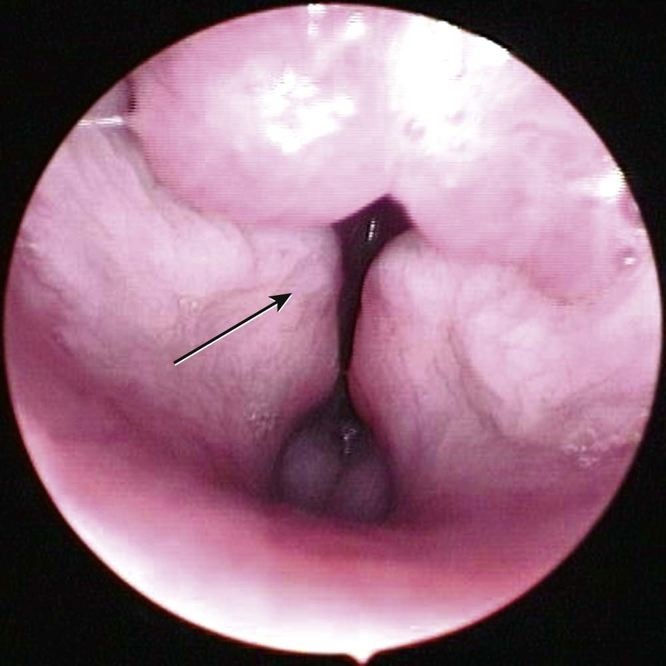

Stage II laryngeal collapse with eversion of laryngeal saccules ventrally and medial collapse (arrow) of the cuneiform processes